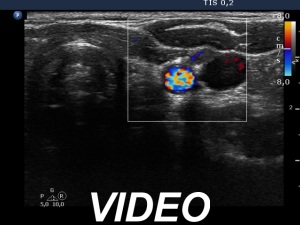

Ultrasonography revealed that the discrete hypoechoic lesion in the left lobe had increased in size, the dimensions were 4x4x5 mm, width, depth and length, respectively. There was a lymph node lateral to the left lobe. The node presented a heterogeneous pattern and lacked a regular hilum.Suggestion: repeat ultrasound in 3 to 6 months.

However, the lymph node is suspicious, especially due to its heterogeneity.